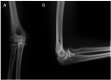

Radiographs at the final follow-up of 3.5 years postoperatively. Anteroposterior view (A) and lateral view (B). Heterotopic ossification at the medial side of the elbow joint and degenerative changes around the radiocapitellar joint (RCJ) were observed.

Figure 5.